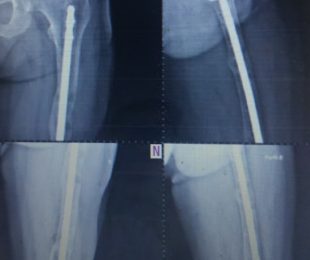

9 – Perdas Ósseas Segmentares